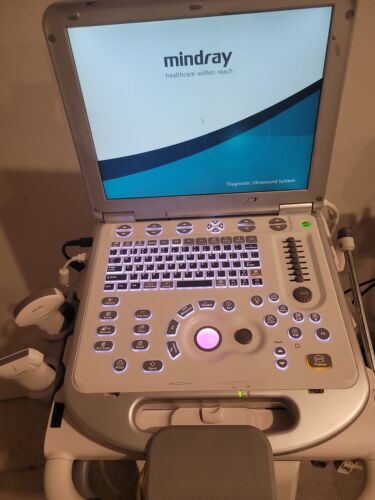

Mindray M7 Portable Ultrasound System with Cart and 2 probes

Regular price $5,999.00 USDRegular priceUnit price / per -